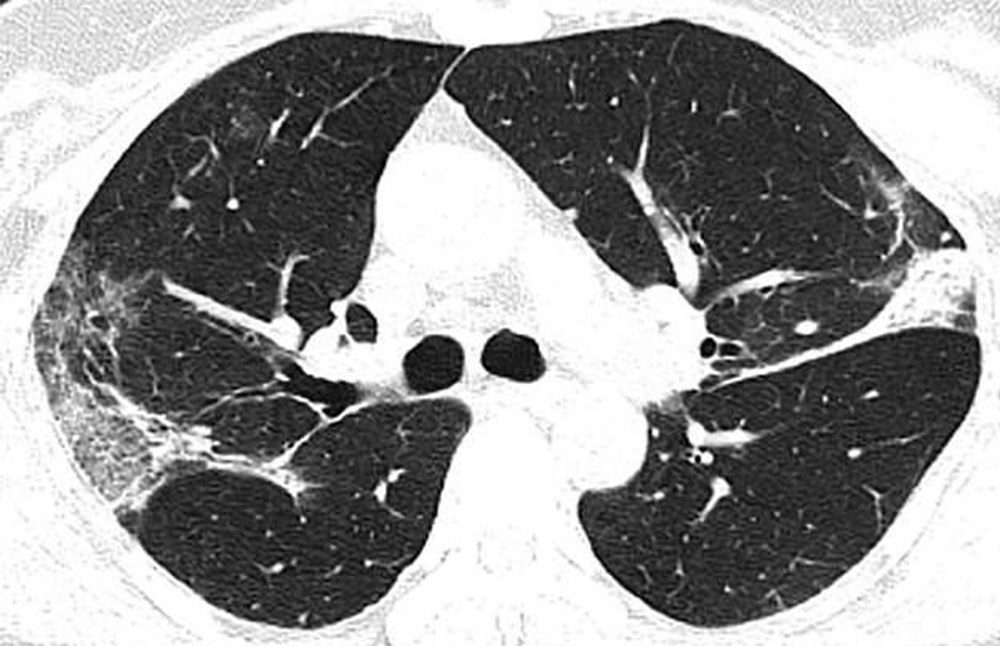

Wuhan'a seyahat ettikten sonra koronavirüse yakalanan 54 yaşında bir kadının bilgisayarlı tomografi taramaları da akciğerlerinde hava boşluklarının kısmen dolduğunu gösteriyor.